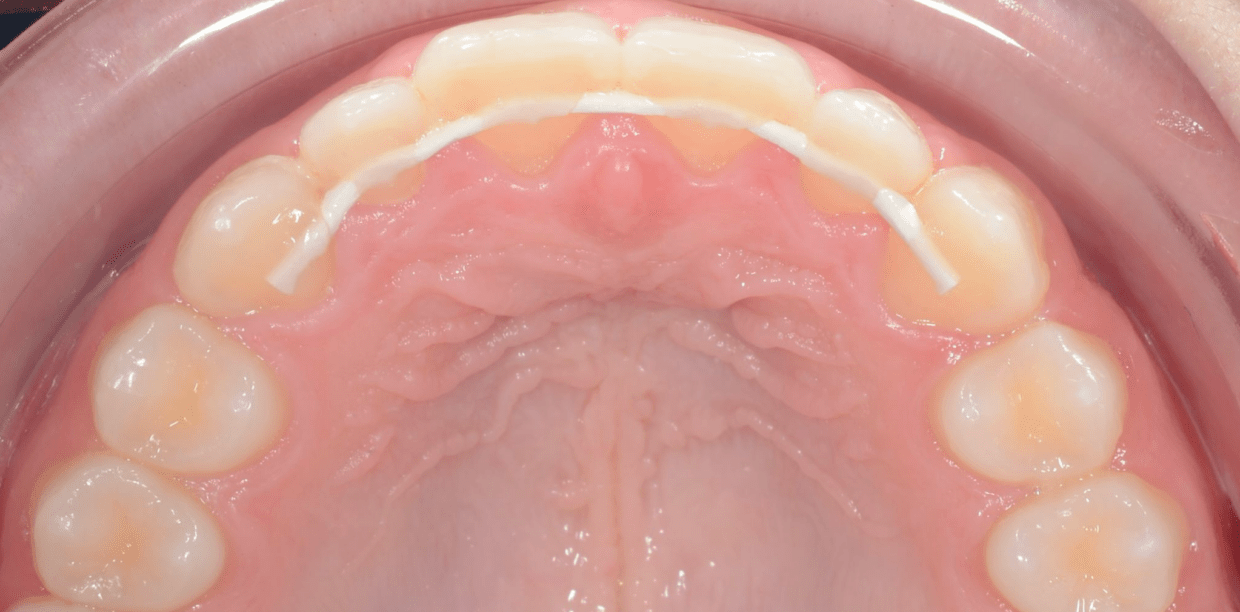

Cas cliniques

Simple - White

Simple - White

Simple - White

Simple - White

Simple - White

Simple - White

Simple - White

Simple - White

Simple - White

Simple - White

Simple - White

Simple - White

Simple - White

Simple - White

Simple - White

Simple - White